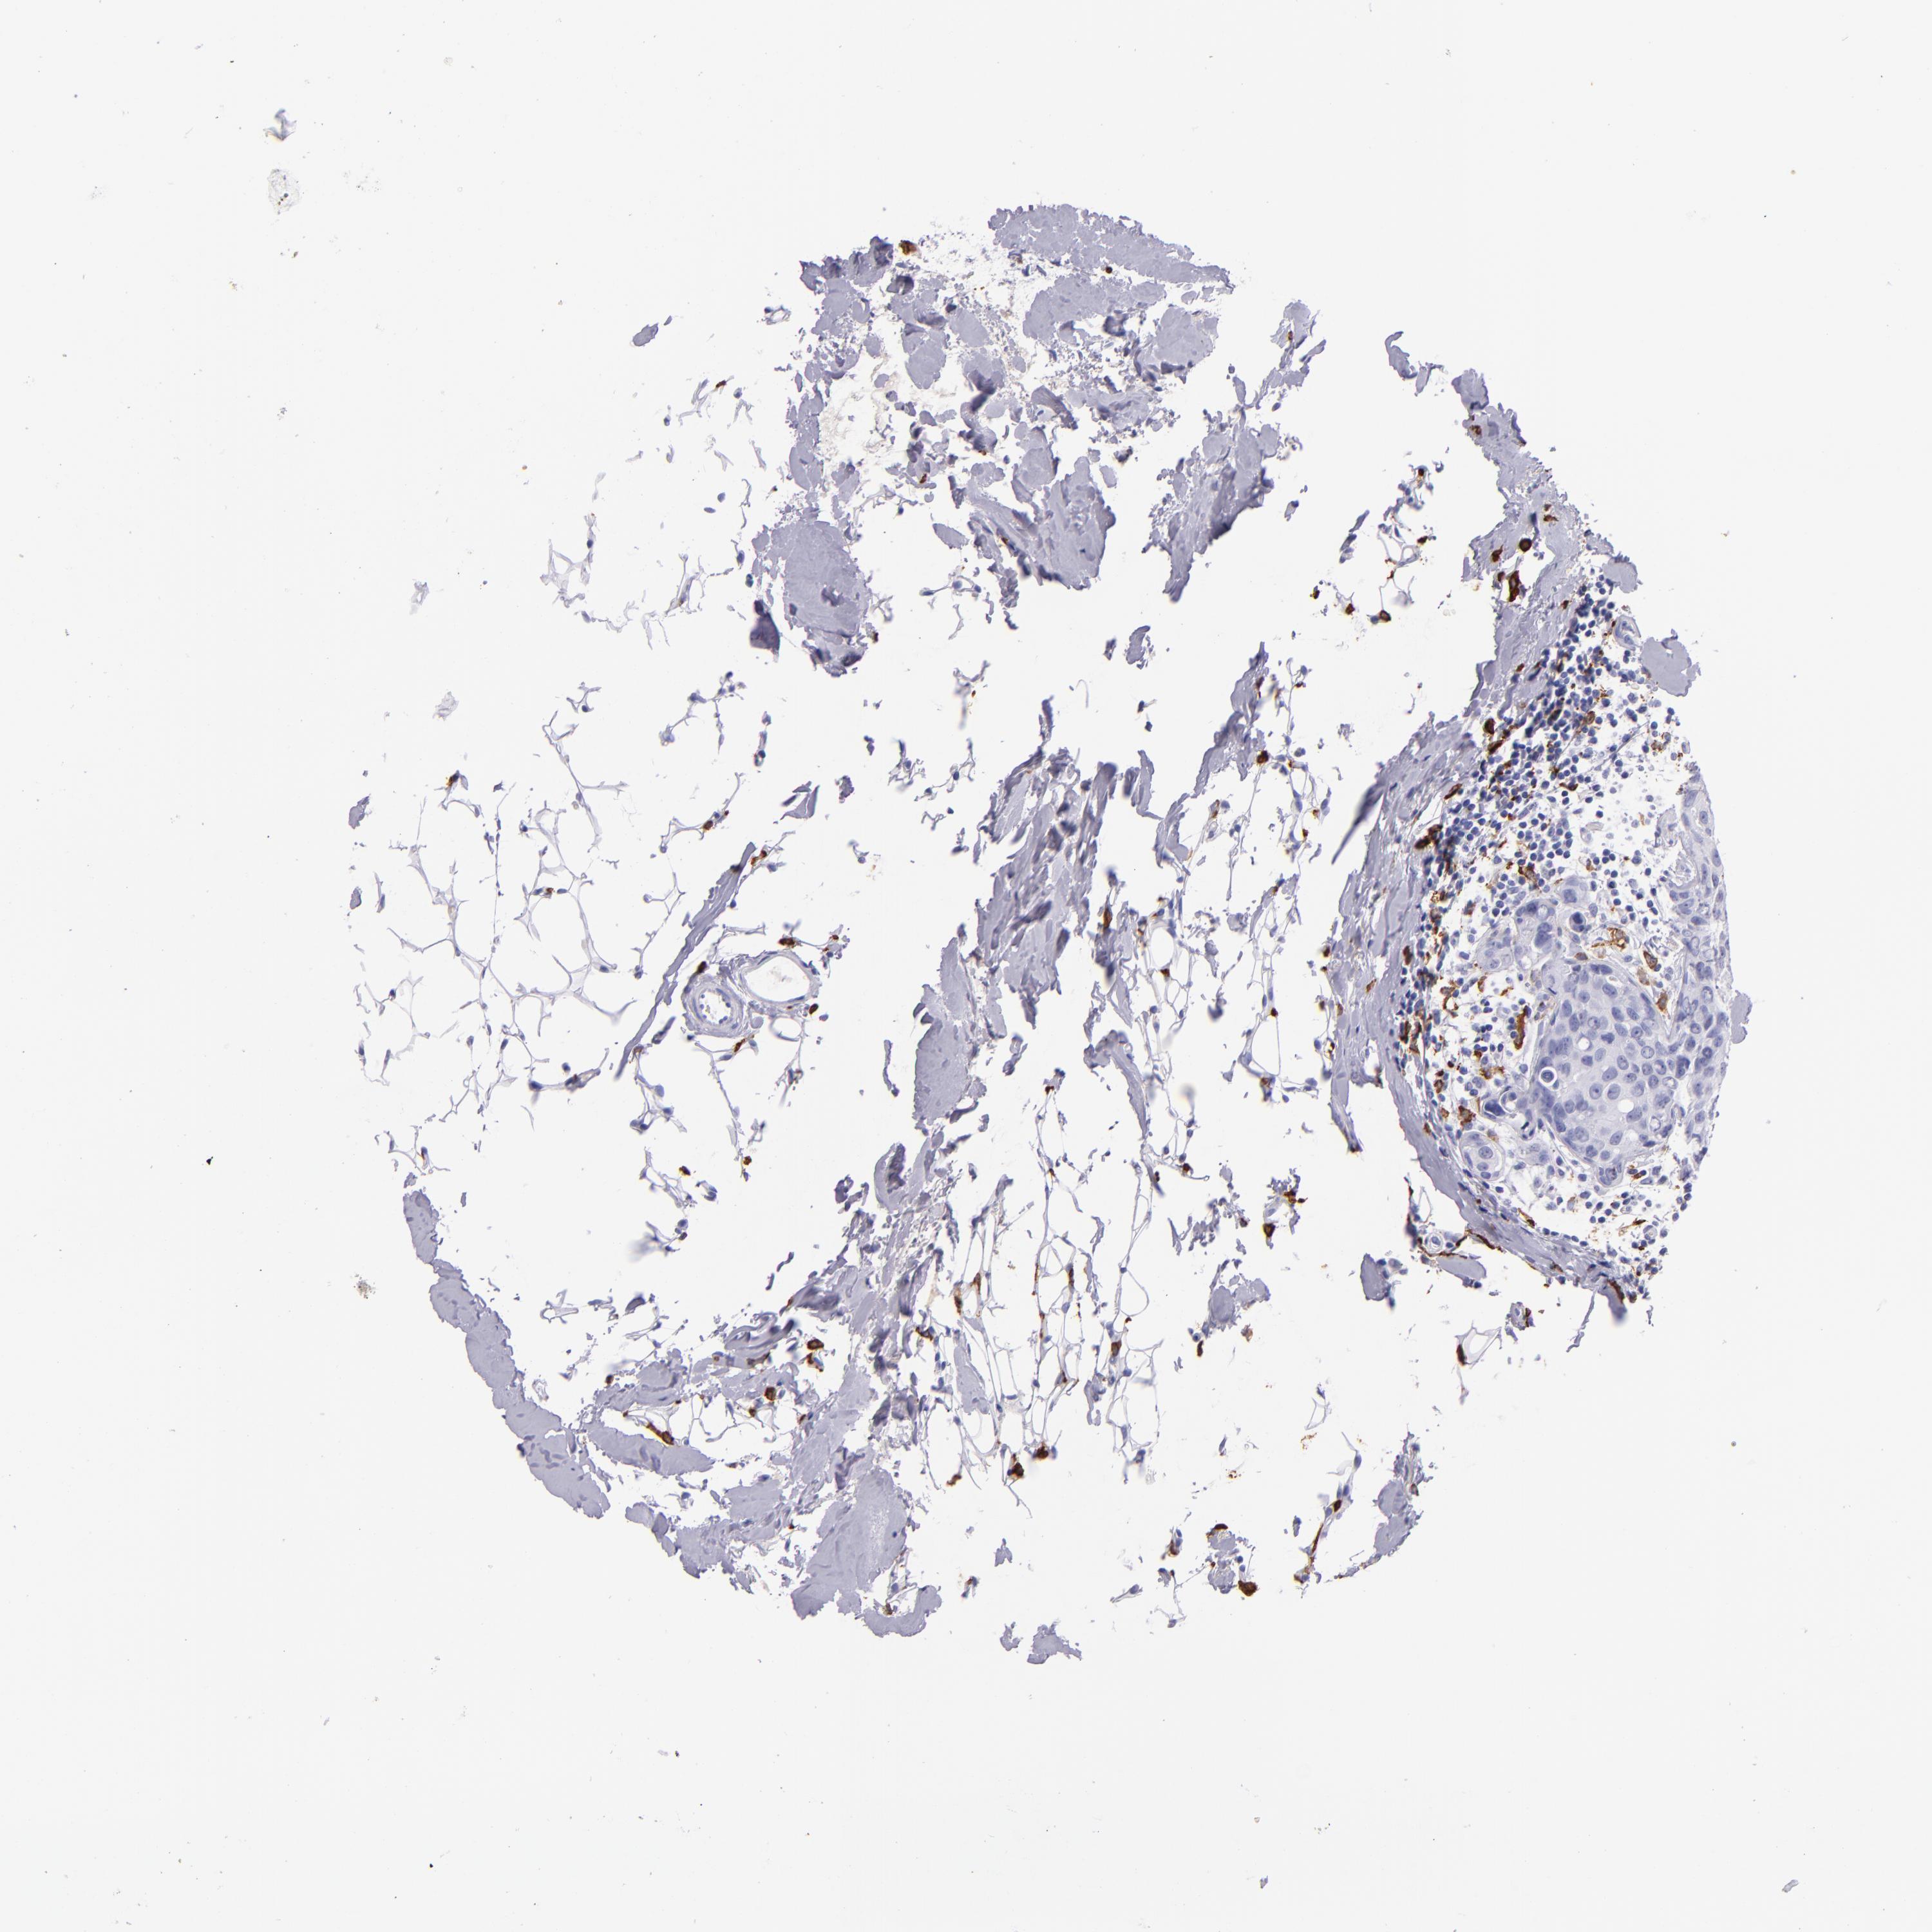

CD163

CANCER BREAST CANCER Show tissue menu

BRCA TCGA BRCA VALIDATION PROTEIN EXPRESSION